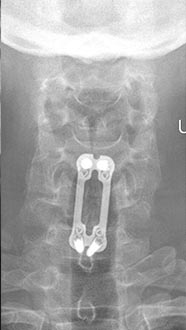

35 year old man presenting with severe neck pain with radiation down the right arm with right bicep weakness. MRI with large right C5-6 disc extrusion.

Postoperative xrays after C5-6 anterior cervical disc replacement. Complete resolution of arm pain and full painless range of motion of his neck.